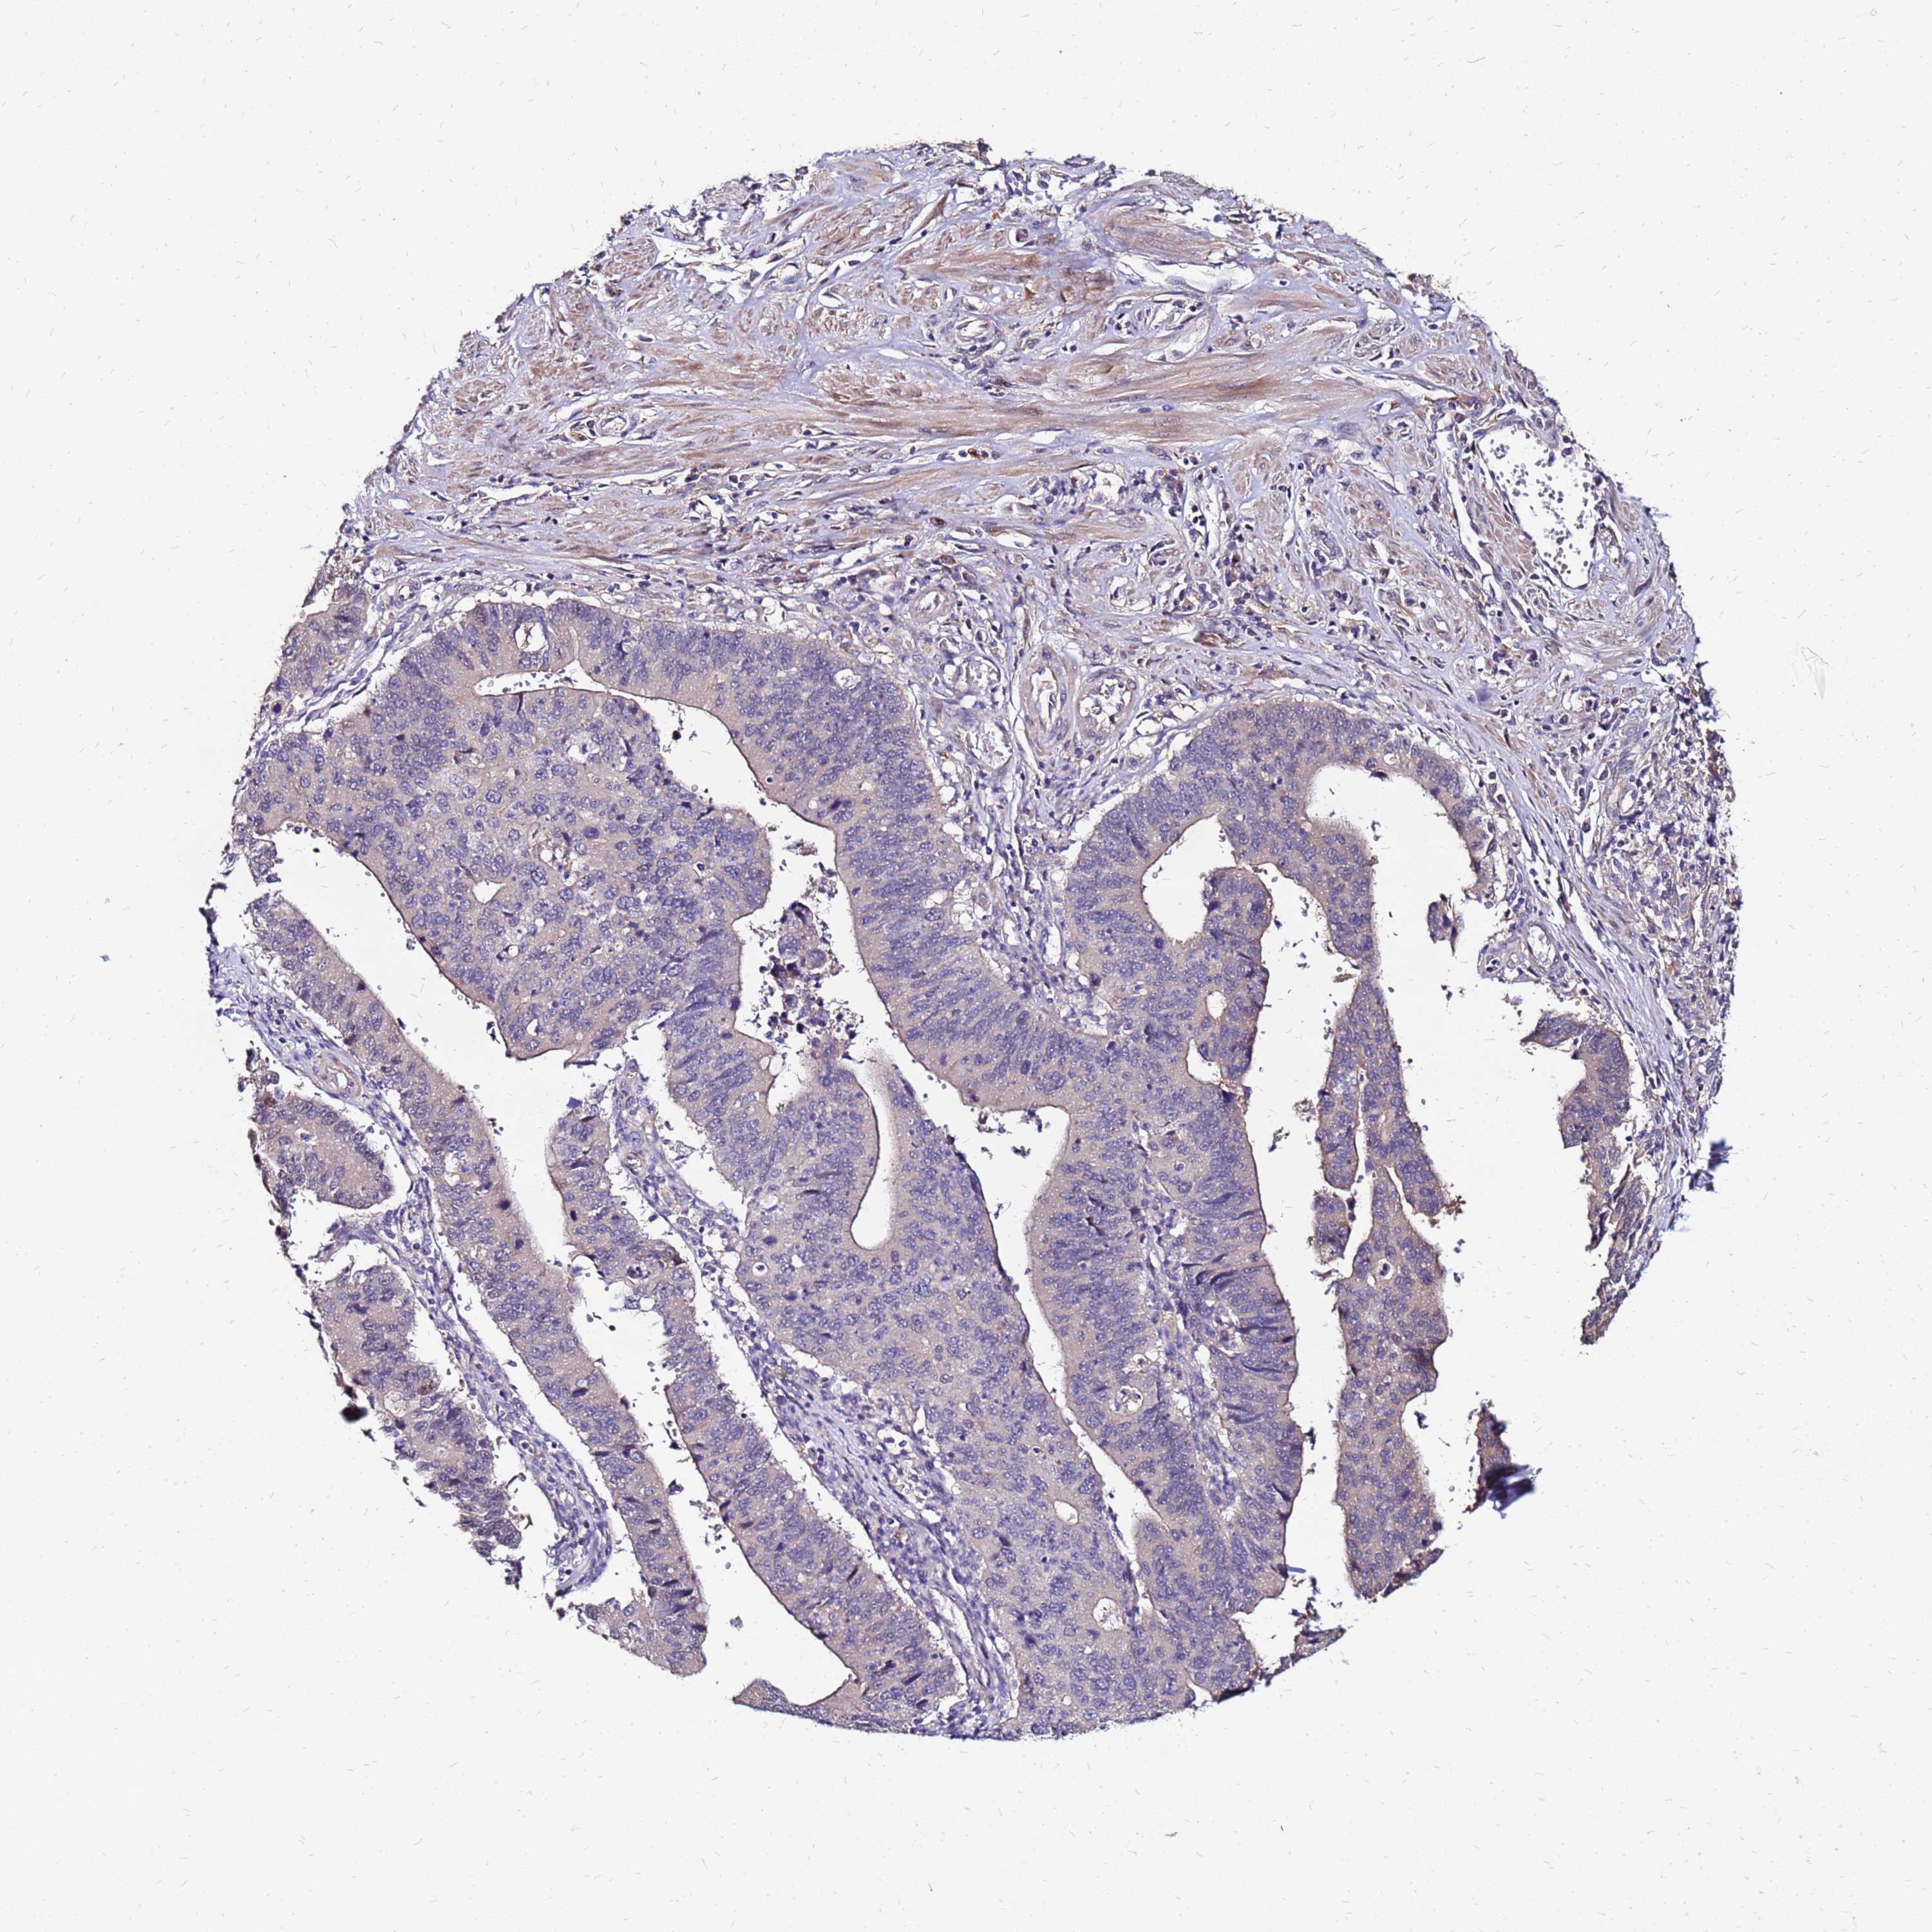

STOMACH CANCER - Protein expressioni

A mouse-over function shows sample information and annotation data. Click on an image to view it in a full screen mode. Samples can be filtered based on level of antibody staining by selecting one or several of the following categories: high, medium, low and not detected. The assay and annotation is described here.

Note that samples used for immunohistochemistry by the Human Protein Atlas do not correspond to samples in the TCGA dataset.

Antibody stainingi

Antibody staining in the annotated cell types in the current human tissue is reported as not detected, low, medium, or high, based on conventional immunohistochemistry profiling in selected tissues. This score is based on the combination of the staining intensity and fraction of stained cells.

Each image is clickable and will lead to virtual microscopy that enables deeper exploration of all samples and also displays staining intensity scores, fraction scores and subcellular localization as well as patient and tissue information for each sample.

Antibody HPA044188

Antibody HPA045619

Antibody HPA045699

Staining

High

Medium

Low

Not detected

Intensity

Strong

Moderate

Weak

Negative

Quantity

>75%

75%-25%

<25%

None

Location

Nuclear

Cytoplasmic/membranous

Cytoplasmic/membranous,nuclear

Adenocarcinoma, NOS